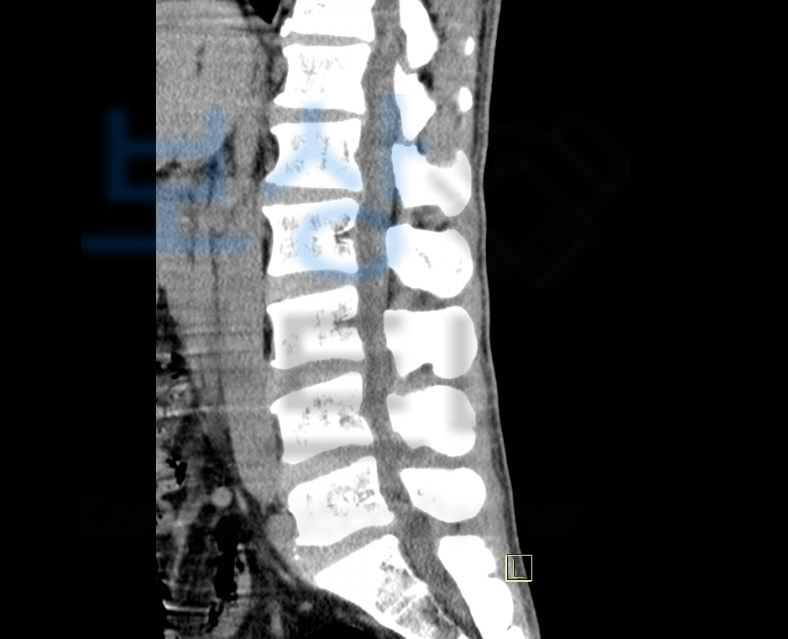

위 진단서 내용처럼 늑골을 침범한 다발골절 S22430 뿐만 아니라

요추 1-3번 골절 S32020, 30, 40

의 진단을 받으셨죠. 위 진단으로 5주간의 요양을 요했지만 척추의 골절은 시간이 경과하면 할수록 몸의 하중에 의해 점점 찌그러지는 형태로 골절이 진행됩니다.

지급받을 수 있었습니다! 게다가 척추, 흉추, 요추 의 골절이시면 더더욱 후유증, 장해 보상 알아 보셔야 합니다.